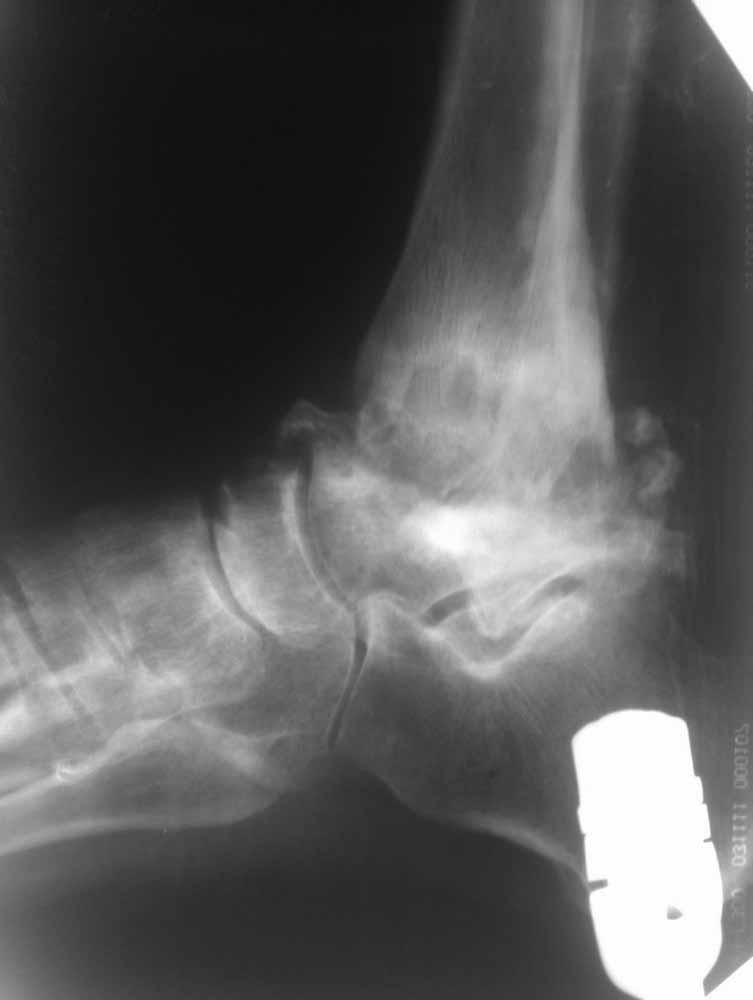

Склоняемся к мысли, что все таки Charcot's Joint.

Планируем артродез стержнем правого голеностопа + аппарат на левый голеностоп.

Остается вопрос - как монтировать ? одномоментно корректировать или все таки постепенно аппаратом?

Вложение не в текстовом формате было извлечено…

Имя     : правый фас.jpg

Тип     : image/jpg

Размер  : 19527 байтов

Описание: отсутствует

Url     : http://weborto.net:8080/pipermail/ortho/attachments/20111203/f37772b8/attachment-0007.jpg